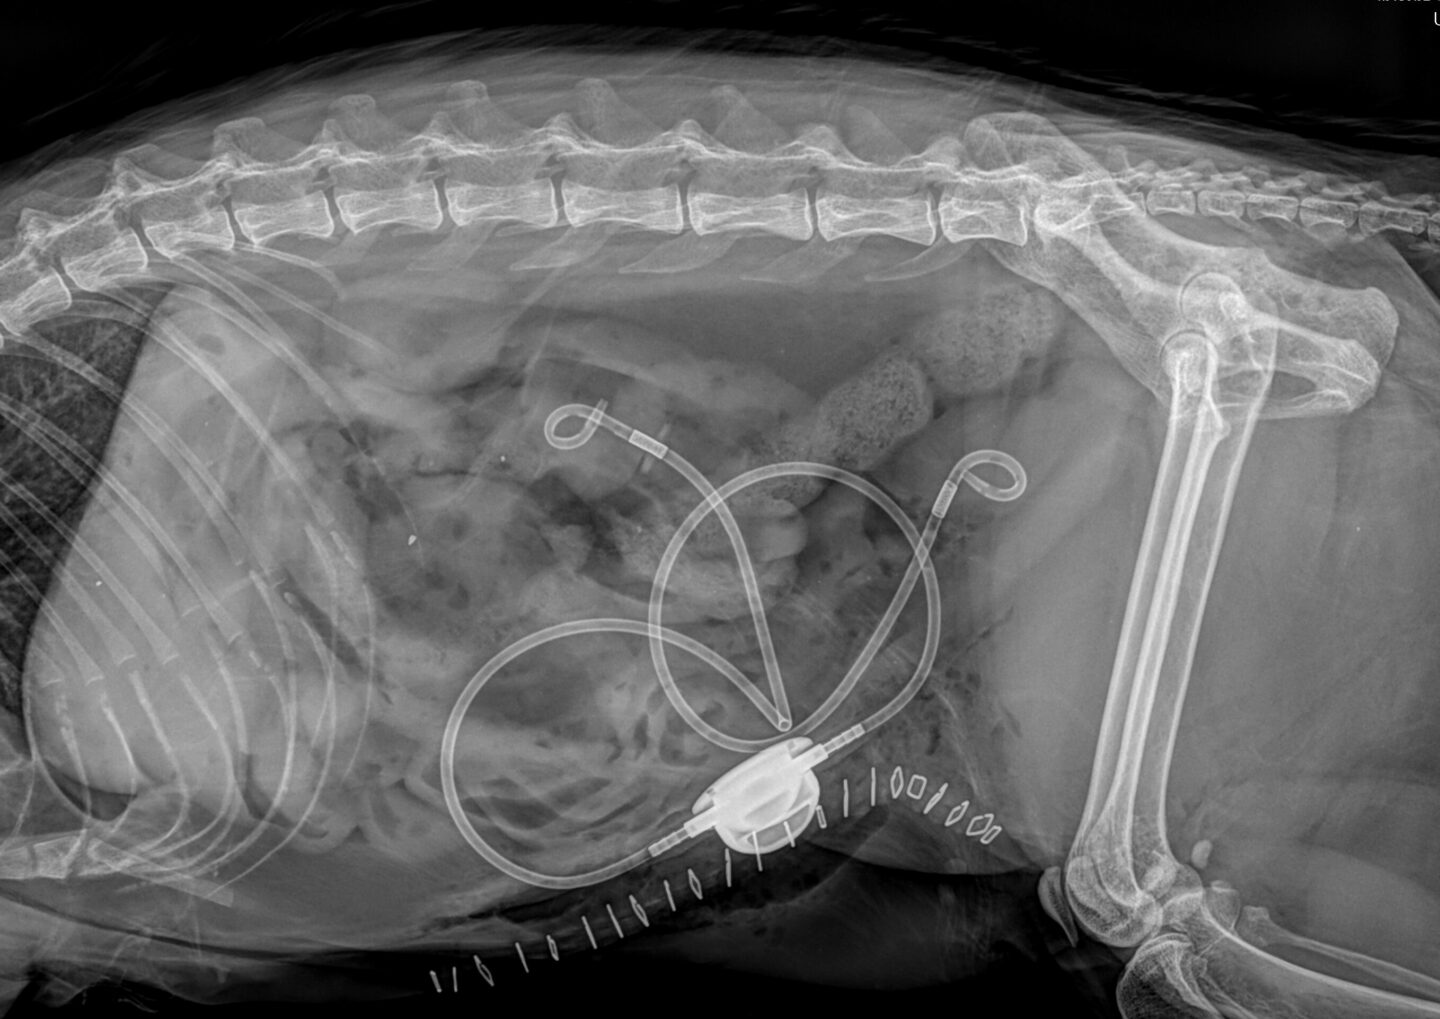

Akuter Schub der chronischen Nierenerkrankung bei der Katze

Die akute Nierenerkrankung ist definiert als abrupte Schädigung des Nierenparenchyms bei gleichzeitig vorliegender chronischer Nierenerkrankung. Die chronische Nierenerkrankung ist eine strukturelle und/oder funktionelle Veränderung mindestens einer Niere, die bereits seit drei Monaten besteht. Die genaue Differenzierung zwischen einer akuten, chronischen und akut auf chronischen Nierenerkrankung kann einige Schwierigkeiten bereiten. Im Fall einer akut auf chronischen Nierenerkrankung ähneln die klinischen Symptome sowie die Laborbefunde einer akuten Nierenerkrankung.